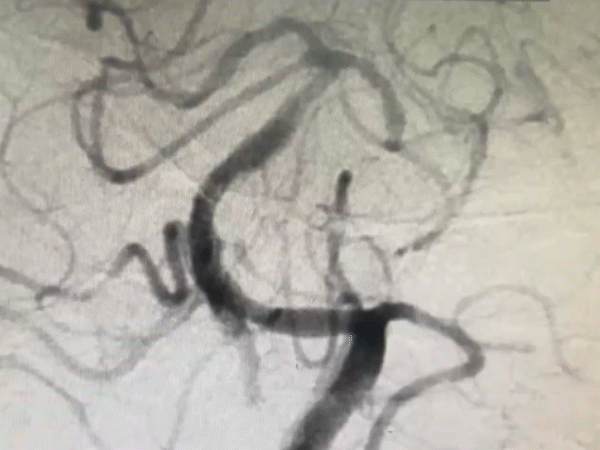

既往影像检查

导丝怎么扩【载药时代 球扩天下】NOVA DES®颅内药物洗脱支架在颅内富穿支区域使用体会二例!_https://www.jmylbn.com_新闻资讯_第25张

DWI

重要影像结论:颅脑MR示桥脑左侧部及双侧基底节区、侧脑室周围、放射冠、半卵圆中心、额顶叶皮层下见散在多发梗死灶

导丝怎么扩【载药时代 球扩天下】NOVA DES®颅内药物洗脱支架在颅内富穿支区域使用体会二例!_https://www.jmylbn.com_新闻资讯_第26张

导丝怎么扩【载药时代 球扩天下】NOVA DES®颅内药物洗脱支架在颅内富穿支区域使用体会二例!_https://www.jmylbn.com_新闻资讯_第27张

DSA

重要影像结论:基底动脉重度狭窄。